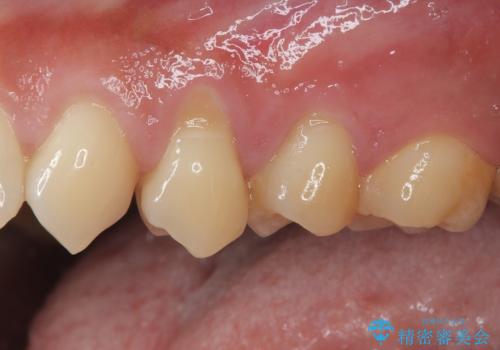

- 歯肉退縮による知覚過敏を気にして来院された患者様です。

診察したところ、知覚過敏をむし歯と勘違いし、一生懸命磨いたことで横縞模様ができるほどでした。

歯肉退縮に対して、上顎からの結合組織移植術(CTG)により、歯根の被覆を行うとともに、歯肉の厚みを増すことで将来の退縮リスクを抑制することとしました。

被覆量が不十分の場合には、追加で手術を行うことで患者様の了解を得ました。